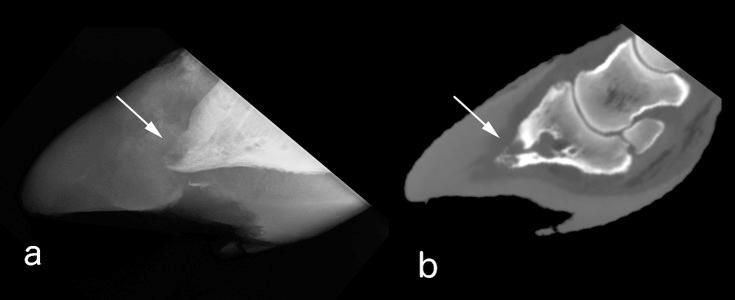

Twenty-one limbs of bovine cadavers (42 digits) were exposed to interdigital cassetteless imaging plate using computed radiography. The radiographic findings included exostosis, a rough planta surface, osteolysis of the apex of the distal phalanx and widening of the laminar zone between the distal phalanx and the hoof wall. All these findings were confirmed by computed tomography. The hindlimbs (19 digits) showed more changes than the forelimbs (10 digits), particularly in the lateral distal phalanx. The cassetteless computed radiography technique is expected to be an easily applicable method for the distal phalanx rather than a conventional cassette-plate and/or the film-screen cassetteless methods.